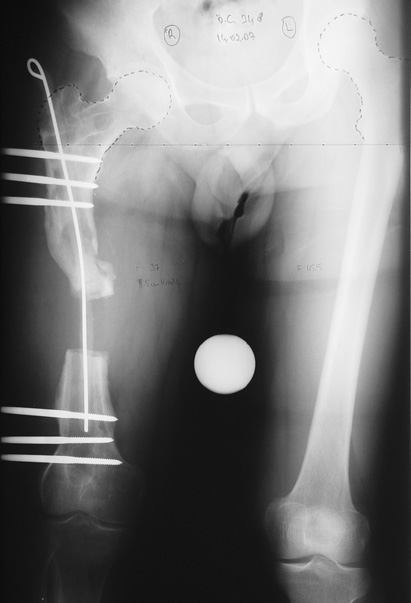

Appropriate radical debridement necessitates excision of all necrotic bone and soft tissues, and frequently causes instability at the involved extremity. The remaining bone and soft tissue defect has to be fixed and reconstructed. The distraction osteogenesis method of Ilizarov is used successfully for achievement of union, correction of the deformity, elimination of limb length inequality and reconstruction of segmental bone defects.

The duration of external fixation (external fixation index) depends on the amount of distraction required, and the extremity is prone to complications during this period. After the distraction phase is completed, the external fixator remains in place during the consolidation phase, which lasts twice as long as the distraction phase; but this period is hardly tolerated. If the external fixator is removed before sufficient consolidation is achieved, fractures, deformity and shortness will be the result. In our department, ‘lenghthening over nail’ method is used in order to decrease the external fixation index and increase patient comfort and activity level. In this method, the intramedullary nail is statically locked after the completion of the distraction phase, and external fixator is removed. The extremity is stabilized by the intramedullary nail during consolidation phase. In this way, complications due to long external fixation index or early removal of the external fixator are avoided.

Case 1